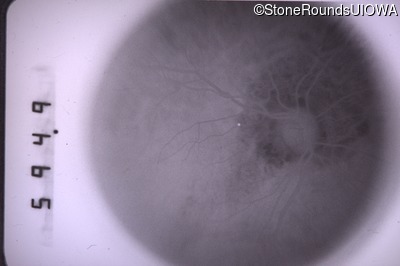

Infrared Fundus Photograph - Right - 20/30 +2

Exemplar